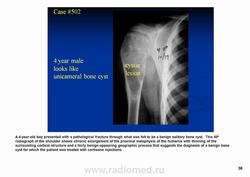

Телеангиэктатическая остеосаркома - редкий (составляет около 4% всех остеосарком) вариант остеосаркомы, характеризующийся наличием кист, заполненных кровью. При рентгенологическом исследовании обычно выявляется полностью литическое поражение без признаков склерозирования, интенсивное вздутие кортикальной пластинки и ее деструкция, часто обнаруживаются периостальная реакция и распространение патологического процесса в мягкие ткани. Гистологическая диагностика телеангиэктатического варианта остеосаркомы может быть относительно несложной при наличии атипичного остеогенеза и высокой степени анаплазии клеточных элементов. Однако довольно часто, особенно у детей и подростков, диагностика вызывает значительные трудности, так как эта остеосаркома, в основном, представлена высокодифференцированным вариантом. Последний отличается тем, что опухолевые клетки определяются только в области выстилки кист и полостей опухоли, злокачественные клетки характеризуются низкой степенью анаплазии, опухолевый остеоид обнаруживается лишь при целенаправленном исследовании серийных срезов, встречаются участки ткани, в которых клеточные элементы и остеоид не имеют признаков атипизма и микроскопическая картина полностью соответствует аневризмальной кисте кости, в связи с чем не исключена диагностическая ошибка при исследовании небольшого количества материала, особенно биопсийного. Относительно медленное развитие опухоли, обычно чисто литическое поражение кости, сходство рентгенологической картины с аневризмальной кистой или гигантоклеточной опухолью кости также способствуют постановке неверного диагноза.

Телеангиэктатическая остеосаркома относится к остеолитическим вариантам обыкновенной интрамедуллярной остеосаркомы и содержит кистовидные сосудистые полости, разделенные тонкими костными перегородками. В некоторых случаях эта опухоль симулирует аневризматичесую костную кисту. Частота такого варианта составляет 0,4—12 % от общего числа остеосарком. Патологический перелом к моменту диагностики встречается более чем у 25 % больных, тогда как лиц с обыкновенной остеосаркомой — не более чем 5 %. У пациентов старшей возрастной группы, а также лиц с поражением костей осевого скелета развитие телеангиэктатической остеосаркомы происходит на фоне болезни Педжета. Макроскопически эта опухоль имеет вид то крупного сгустка крови или некротической массы, то многокамерной кисты, содержащей жидкую кровь, как это бывает в аневризматической костной кисте.

Рентгенологически выявляют метафизарную локализацию, полностью литическое поражение без признаков оссификации, часто интенсивное вздутие кости и её деструкцию, формирование мягкотканого компонента, иногда периостальную реакцию.